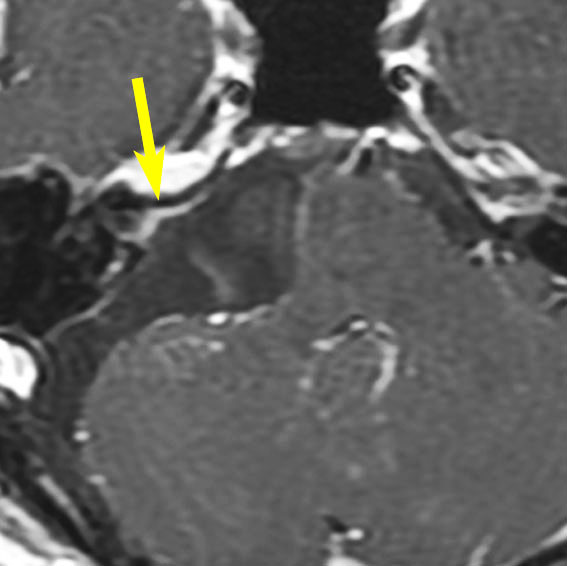

腫瘍が嚢胞性拡大で大きくなって,腫瘍内出血して,閉塞性水頭症になって意識障害を生じた患者さんです。このような事態になると臨時手術で腫瘍を摘出します。

大きなのう胞性聴神経腫瘍です。いくつかの袋が重なって腫瘍を形成しています。橋や延髄(脳幹部)が変形して,第4脳室がつぶれて閉塞しています。袋の周りが白く線状に造影されているのですが,この袋の壁だけに腫瘍細胞がありますから,これを剥がすように摘出します。顔面神経が薄くなって袋の壁にくっついているのですが,袋を破ってくしゃくしゃにすると顔面神経の位置が変わってしまって,顔面神経を損傷することがあるので要注意です。のう胞性聴神経腫瘍の方が顔面神経麻痺の後遺症の頻度が高いという報告もあるくらいです。この患者さんは迷走神経と舌咽神経の圧迫も強くて,ご飯を飲み込むことが難しくなっていました(嚥下障害)。

また,この患者さんは急に容態が悪くなって意識障害となりました。何故なら腫瘍の内部で出血したからです(黄色の矢印の部分)。第4脳室が詰まって閉塞性水頭症になって側脳室が拡大しています(右の画像)。